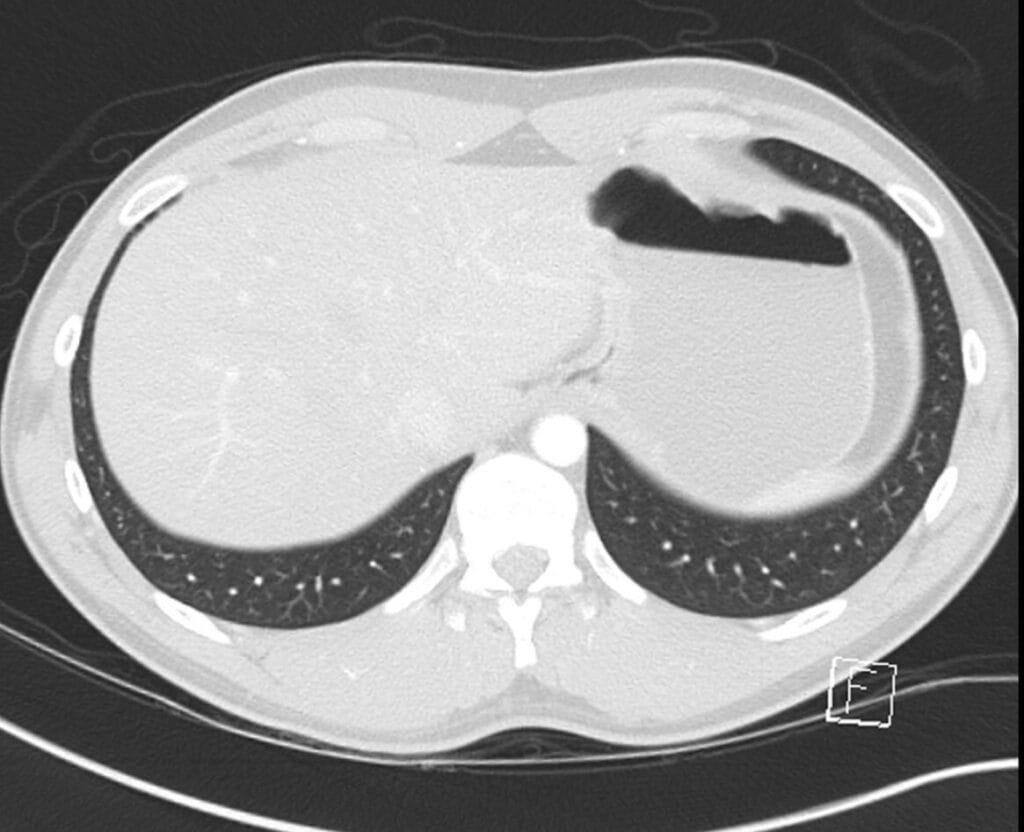

57. anterior costophrenic recess

58. lateral costophrenic recess

59. posterior costophrenic recess